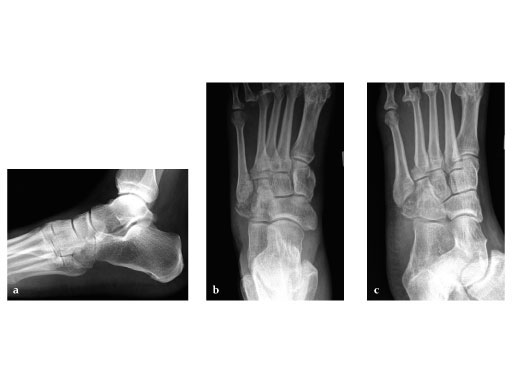

Case provided by Andrew K Sands, New York, US